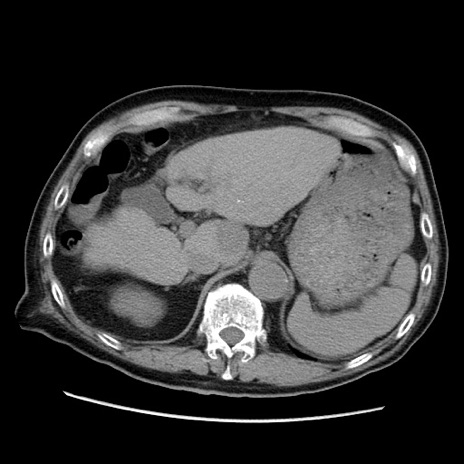

症例21(横断像)

【症例】70歳代男性

【現病歴】肝硬変・肝細胞癌にてかかりつけの方。約9時間前に食後より腹痛出現。症状が徐々に増悪し、嘔吐出現したため来院。

【既往歴】肝硬変、肝細胞癌(RFA、TACE後)

【身体所見】意識清明、表情苦悶様、BT 36℃、BP 129/78mmHg、P 88bpm、SpO2 97%(RA)、右上腹部から心窩部にかけて圧痛あり、反跳痛なし、筋性防御あり。